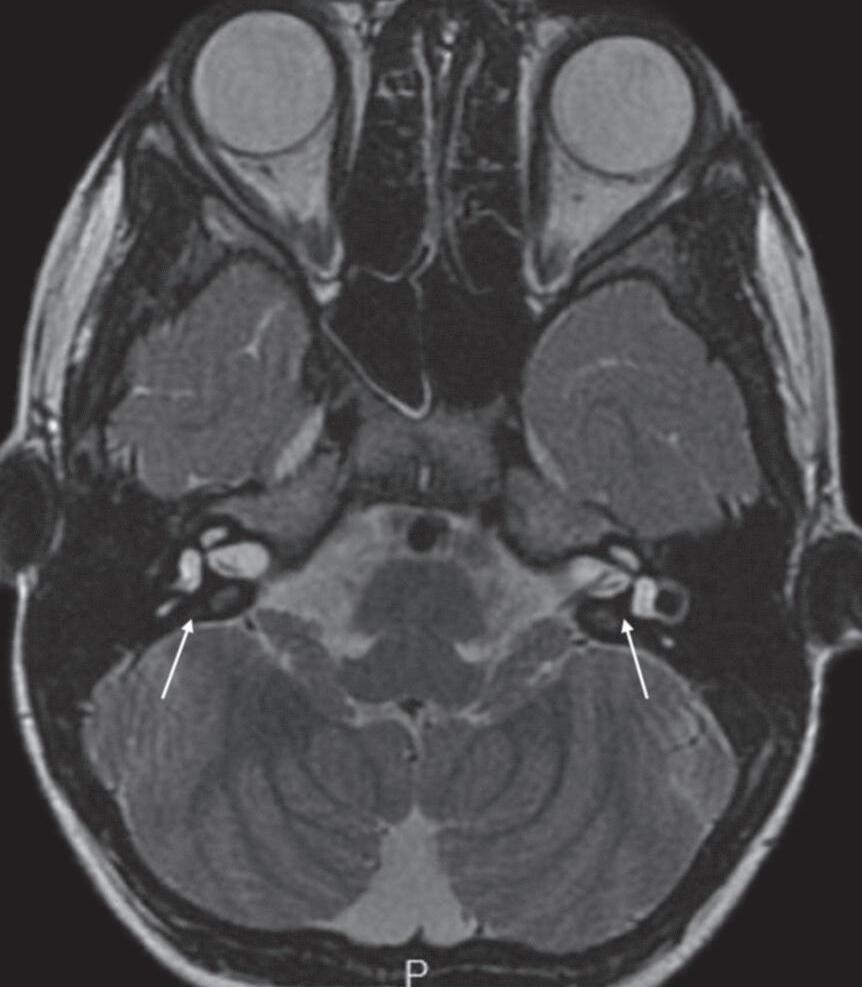

A sequência gradiente-eco balanceado steady state (FIESTA, CISS, TrueFISP) é uma sequência muito rápida, com aquisição volumétrica das imagens, adquiridas com espessura de corte muito fina e sem intervalo entre os cortes. Esta sequência demonstra conteúdo fluido de liquor, perilinfa ou endolinfa com sinal hiperintenso, com acurácia, estruturas neurais e a relação com estruturas vasculares na fossa posterior (Figs. 1-12 e 1-13).

Para a avaliação de conflitos neurovasculares as sequências volumétricas (FIESTA, CISS, BALANCE, SPACE, de acordo com os fabricantes) possibilitam o diagnóstico na maioria dos casos, mas podem ser associadas às imagens de angio RNM em casos duvidosos.

Fig. 1-24. Conflito neurovascular da P.I.C.A. com o VIII nervo craniano direito no trajeto cisternal. Sequência volumétrica axial FIESTA (a): P.I.C.A. (seta vermelha curta) em contato com o VIII nervo craniano junto à zona de entrada no tronco cerebral (seta branca longa); angio RNM (3DTOF) (b) P.I.C.A. (seta amarela) projetando-se cranial e lateralmente no trajeto do VIII nervo; imagem de aquisição da angio RNM (c) P.I.C.A. projetando-se junto ao VIII nervo direito (seta branca longa); VIII (seta vermelha curta).